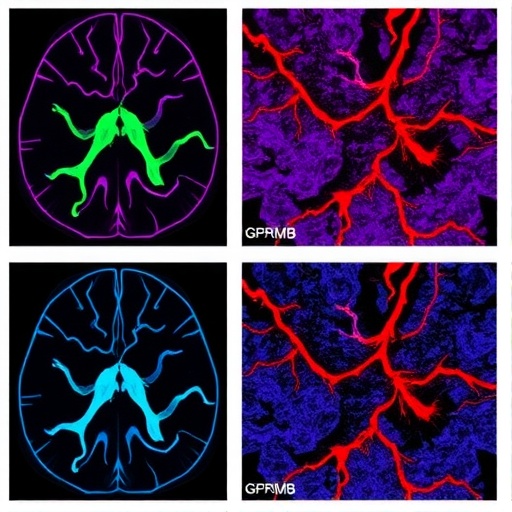

gpnmb+-macrophages-promote-vascular-fibrosis-in-glioblastoma

GPNMB+ Macrophages Promote Vascular Fibrosis in Glioblastoma

January 25, 2026

In a groundbreaking study, a research team led by Du, Long, and Li has unveiled the intricate relationship between spatially-reprogrammed…

Read More